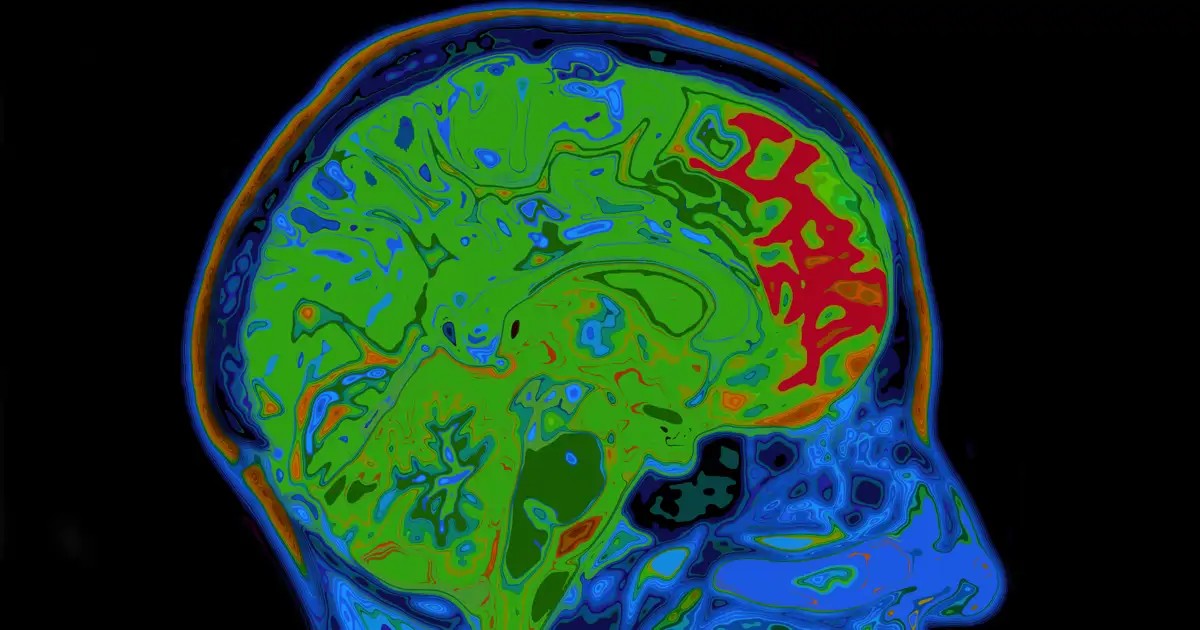

Im Verlauf der Untersuchung identifizierten die Wissenschaftler einen fundamentalen neurobiologischen Mechanismus, der erheblichen Einfluss darauf hat, wie schnell das Gehirn Belohnungsassoziationen bildet. Dies wirkt sich sowohl auf die Schaffung von positiven Gewohnheiten als auch auf die Entwicklung von Abhängigkeiten aus. Konkret handelt es sich um das Protein KCC2, das als Katalysator für das assoziative Lernen fungiert und in der Forschung mit einem Schalter verglichen wird.

KCC2 ist ein essentielles Protein für die Homöostase von Chloridionen in Neuronen und moduliert darüber hinaus die Aktivität der Dopamin- ausschüttenden Neuronen, die als Glücksneurotransmitter fungieren. Eine Verringerung der Aktivität dieses Proteins führt zu einem signifikanten Anstieg der Aktivität dopaminergischer Neuronen, was neue Assoziationen zwischen Umgebungsreizen und positiven Ergebnissen beschleunigt.

Das Forscherteam beobachtete im Gehirngewebe von Mäusen und durch Verhaltensversuche, dass die Beziehung invers proportional ist: Je geringer die Anwesenheit von KCC2, desto höher die Sensibilität für Lernprozesse. Weiterhin wurde festgestellt, dass dieses Protein nicht nur die Frequenz der Aktivierung reguliert, sondern auch die Koordination der Neuronen. Diese Koordination ist entscheidend, da synchronisierte neuronale Aktivität eine höhere Dopaminausschüttung fördert.